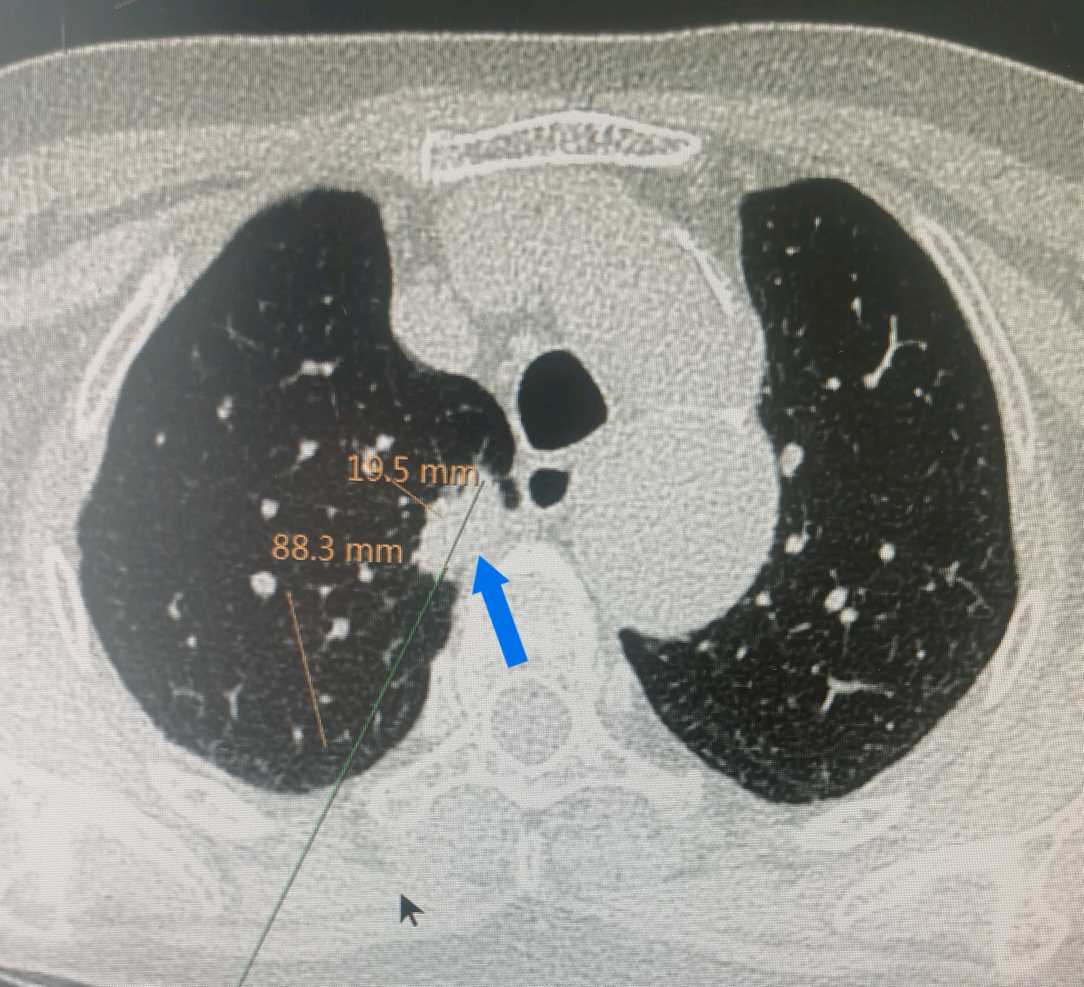

靠近胸膜的结节为何风险高?答案是一旦肿瘤突破胸膜,极容易胸膜腔播散转移,本例为2厘米结节,突破肺表面的胸膜后,出现图1、图2所见的天女散花般转移灶。由1期变为4期,近胸膜的结节相对要积极手,以免肿瘤转移。